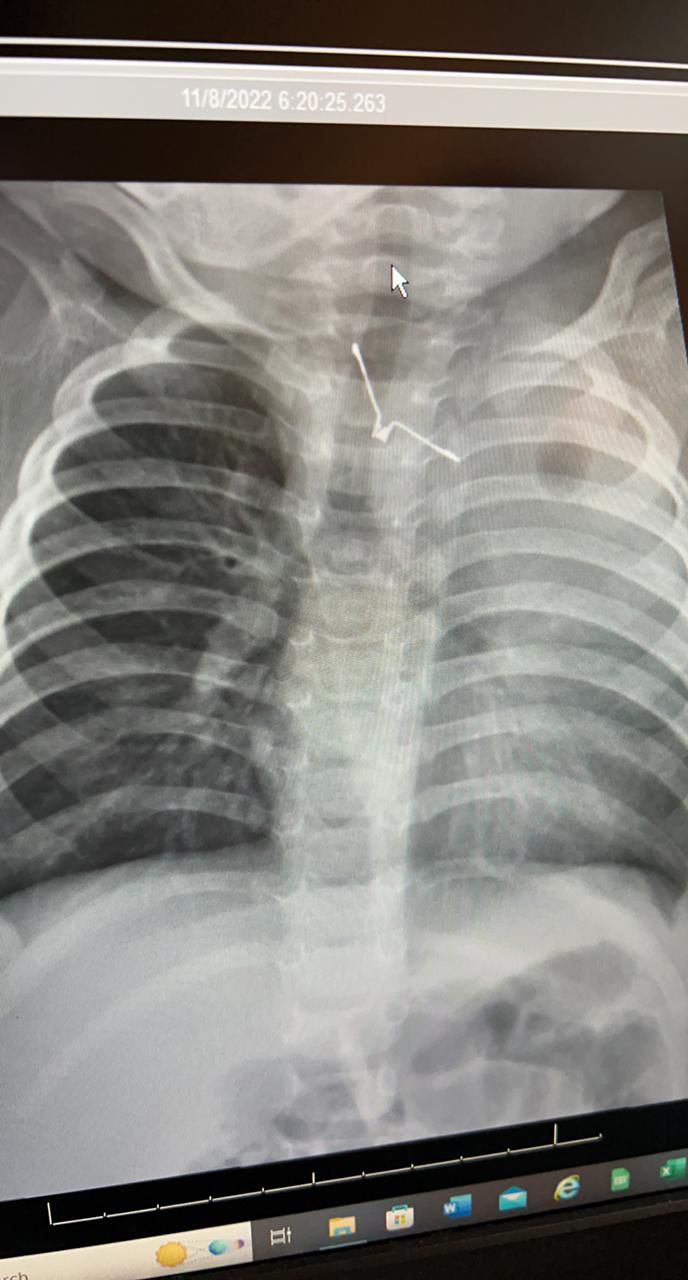

تمكن فريق طبي جراحي من إزالة جسم غريب علق في مرئ طفلة تسبب لها في مضاعفات صحية خطيرة .

حيث أن الطفلة تبلغ من العمر 8 شهور و حضرت إلى طوارىء مستشفى الملك عبدالعزيز و هي تعاني من جفاف شديد و صعوبه في البلع و نقص في الشهية و بكاء مستمر منذ ٥ أيام

من جانبه أكد أن الفريق الطبي المشرف على الحالة قام على الفور بعمل التحاليل و الاشعات اللازمة و إدخال الطفلة لغرفة العمليات بصفه عاجلة و ذلك لإكتشاف جسم معدني حاد الاطراف بلعته الطفله و بقي عالقاً في المرىء مسبباً لها مضاعفات صحية خطيرة خصوصاً لو تم تحريكه بأي طريقه خاطئه ، حيث نجح الفريق الطبي في مده زمنية تقارب الـ ( 4 ) ساعات من اخراج الجسم الغريب بالمنظار و بحذر شديد حتى لا تصاب الأنسجة المحيطة به بأي جروح ، و تتمتع المريضة بصحة جيدة تحت العناية المكثفة لإكمال فترة الشفاء .